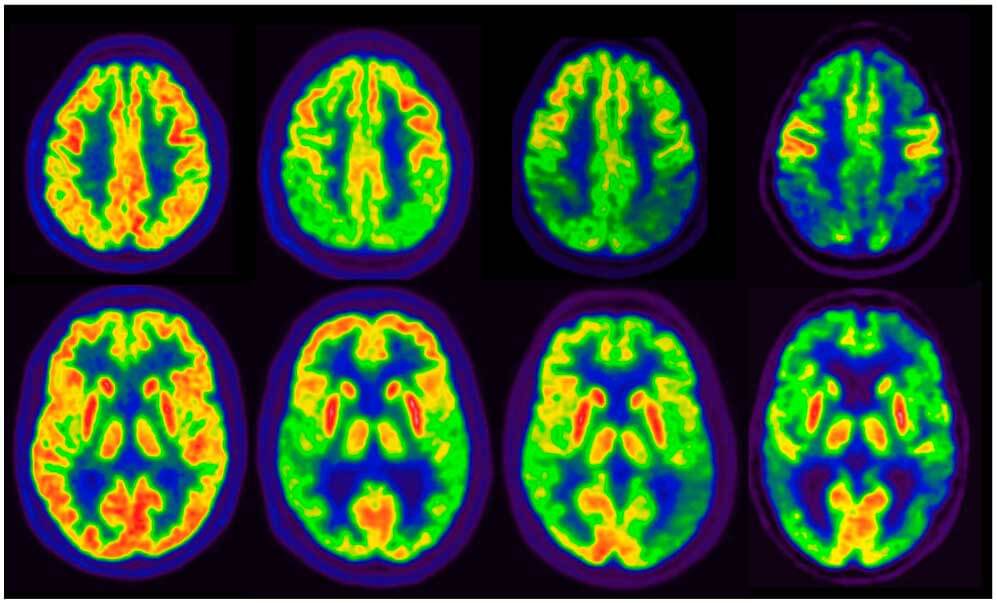

En un estudio observacional de gran tamaño se observó que la tasa de PET cerebral positivo para tau alcanzaba un 10%  en individuos sin deterioro cognitivo, y la combinación de positividad para PET de amiloide beta (Aβ) y tau se asoció con un alto riesgo de progresión clínica, tanto en la etapa preclínica como en la sintomática de la enfermedad de Alzheimer. Estos hallazgos subrayan el potencial de la PET para tau como biomarcador para la estadificación de la enfermedad. JAMA, 16 de junio de 2025.

Pérdida acelerada de volumen cerebral causada por fármacos anti-β-amiloide. Revisión sistemática y metanálisis

Estos hallazgos revelan el potencial de las terapias anti-Aβ para comprometer la salud cerebral a largo plazo al acelerar la atrofia cerebral y brindan una nueva perspectiva sobre el impacto adverso de anormalidades de imagen relacionadas con amiloide. A partir de estos hallazgos se realizan seis recomendaciones. Neurology,  mayo de 2023